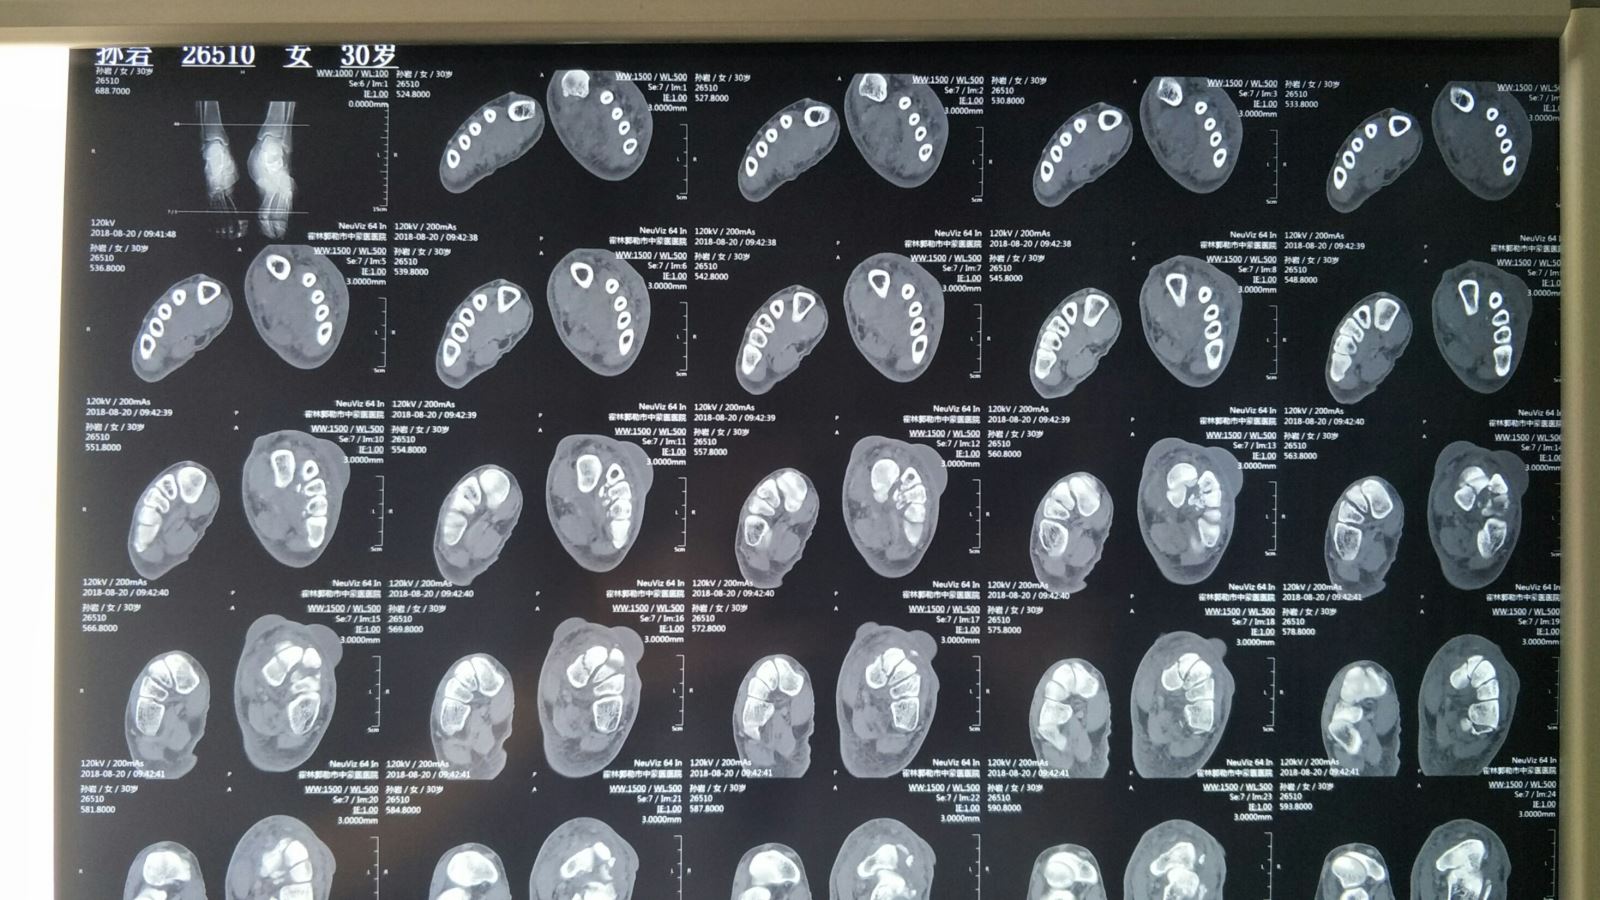

术前CT:Lisfranc关节损伤,跖跗关节脱位,内侧楔骨骨折,Chaopart(跗横关节)脱位,跟骨外侧壁骨折。